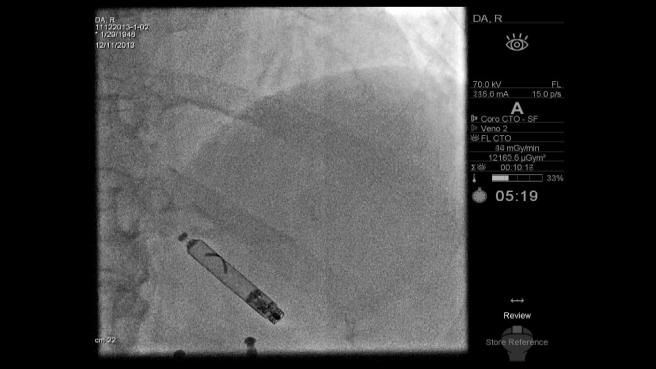

Effettuato a Ravenna il primo impianto di pacemaker wireless in Italia